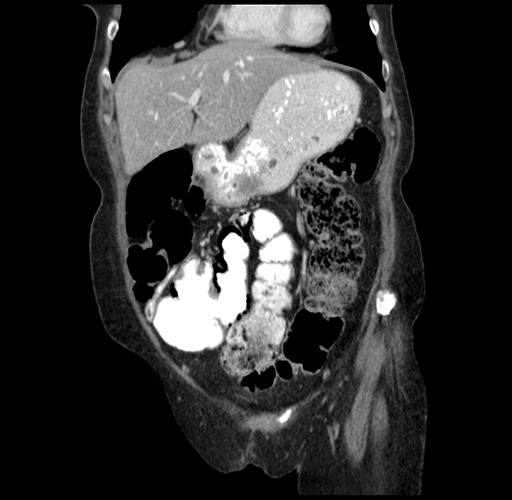

Coronal Venous